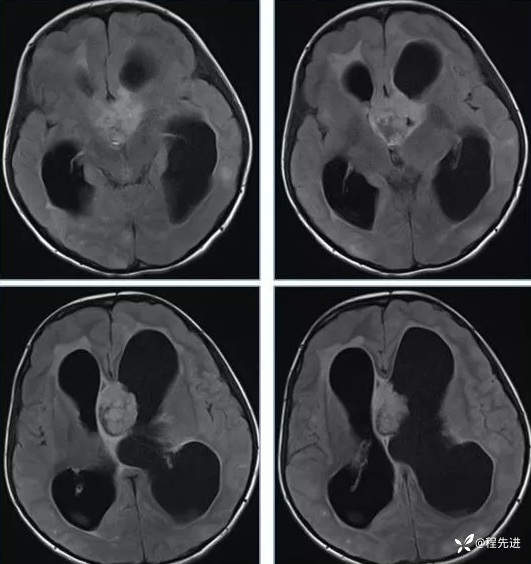

【神经】特别精彩病例|行走不稳2月余

患者性别:男

患者年龄:13岁

主诉:行走不稳2月余

现病史:2个月前患者无明显诱因下出现行走不稳,近期症状逐渐加重,站立不能。病程中患者无意识障碍,无头痛头晕,无明显恶心呕吐、视物旋转、耳鸣、眼球活动障碍等,无尿量增多、泌乳、口干等,体重无明显改变,睡眠可,食欲可,二便正常。

专科检查:右侧肢体肌力III-IV级,左侧肢体肌力IV级,肌张力下降